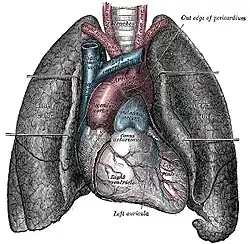

Das Herz liegt innerhalb des Herzbeutels (Perikard) im Mediastinum: Seitlich grenzen, getrennt durch parietale und viszerale Pleura (Brustfell), die linke und rechte Lunge an das Herz. Unten sitzt das Herz dem Zwerchfell auf, das mit dem Herzbeutel verwachsen ist. Oberhalb teilt sich die Luftröhre (Trachea) in die beiden Hauptbronchien (Bifurcatio tracheae), von denen der linke vom Aortenbogen überquert wird. Unterhalb dieser Aufteilung befindet sich der linke Herzvorhof. Wenn dieser krankhaft vergrößert ist, kann das zu einer Spreizung der Hauptbronchien führen, was sich im Röntgenbild als vergrößerter Winkel zwischen den Bronchien darstellt. Der linke Vorhof steht außerdem nach hinten in direktem Kontakt mit der Speiseröhre. Vor dem Herzen befindet sich das Brustbein (Sternum), im oberen Bereich liegt es vor den abgehenden großen Gefäßen. Zwischen Brustbein und Herz liegt der Thymus.

Das Herz liegt also praktisch direkt hinter der vorderen Leibeswand in Höhe der zweiten bis fünften Rippe. Die Herzbasis oben reicht nach rechts etwa zwei Zentimeter über den rechten Brustbeinrand hinaus. Unten kommt die Herzspitze knapp an eine gedachte senkrechte Linie heran, die durch die Mitte des linken Schlüsselbeins verläuft (linke Medioklavikularlinie).

Anatomie

Die Gestalt des Herzens gleicht einem abgerundeten Kegel, dessen Spitze nach unten und etwas nach links vorne weist. Das Herzvolumen entspricht ungefähr dem Volumen der geschlossenen Faust[19] des betreffenden Menschen. Das Herz sitzt beim Menschen in der Regel leicht nach links versetzt hinter dem Brustbein. In seltenen Fällen ist es nach rechts versetzt (die sogenannte Dextrokardie – „Rechtsherzigkeit“), meist bei Situs inversus (also bei spiegelverkehrter Organanordnung).